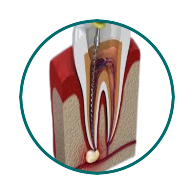

A procedure to save infected or damaged teeth by removing the infected pulp and sealing the tooth.